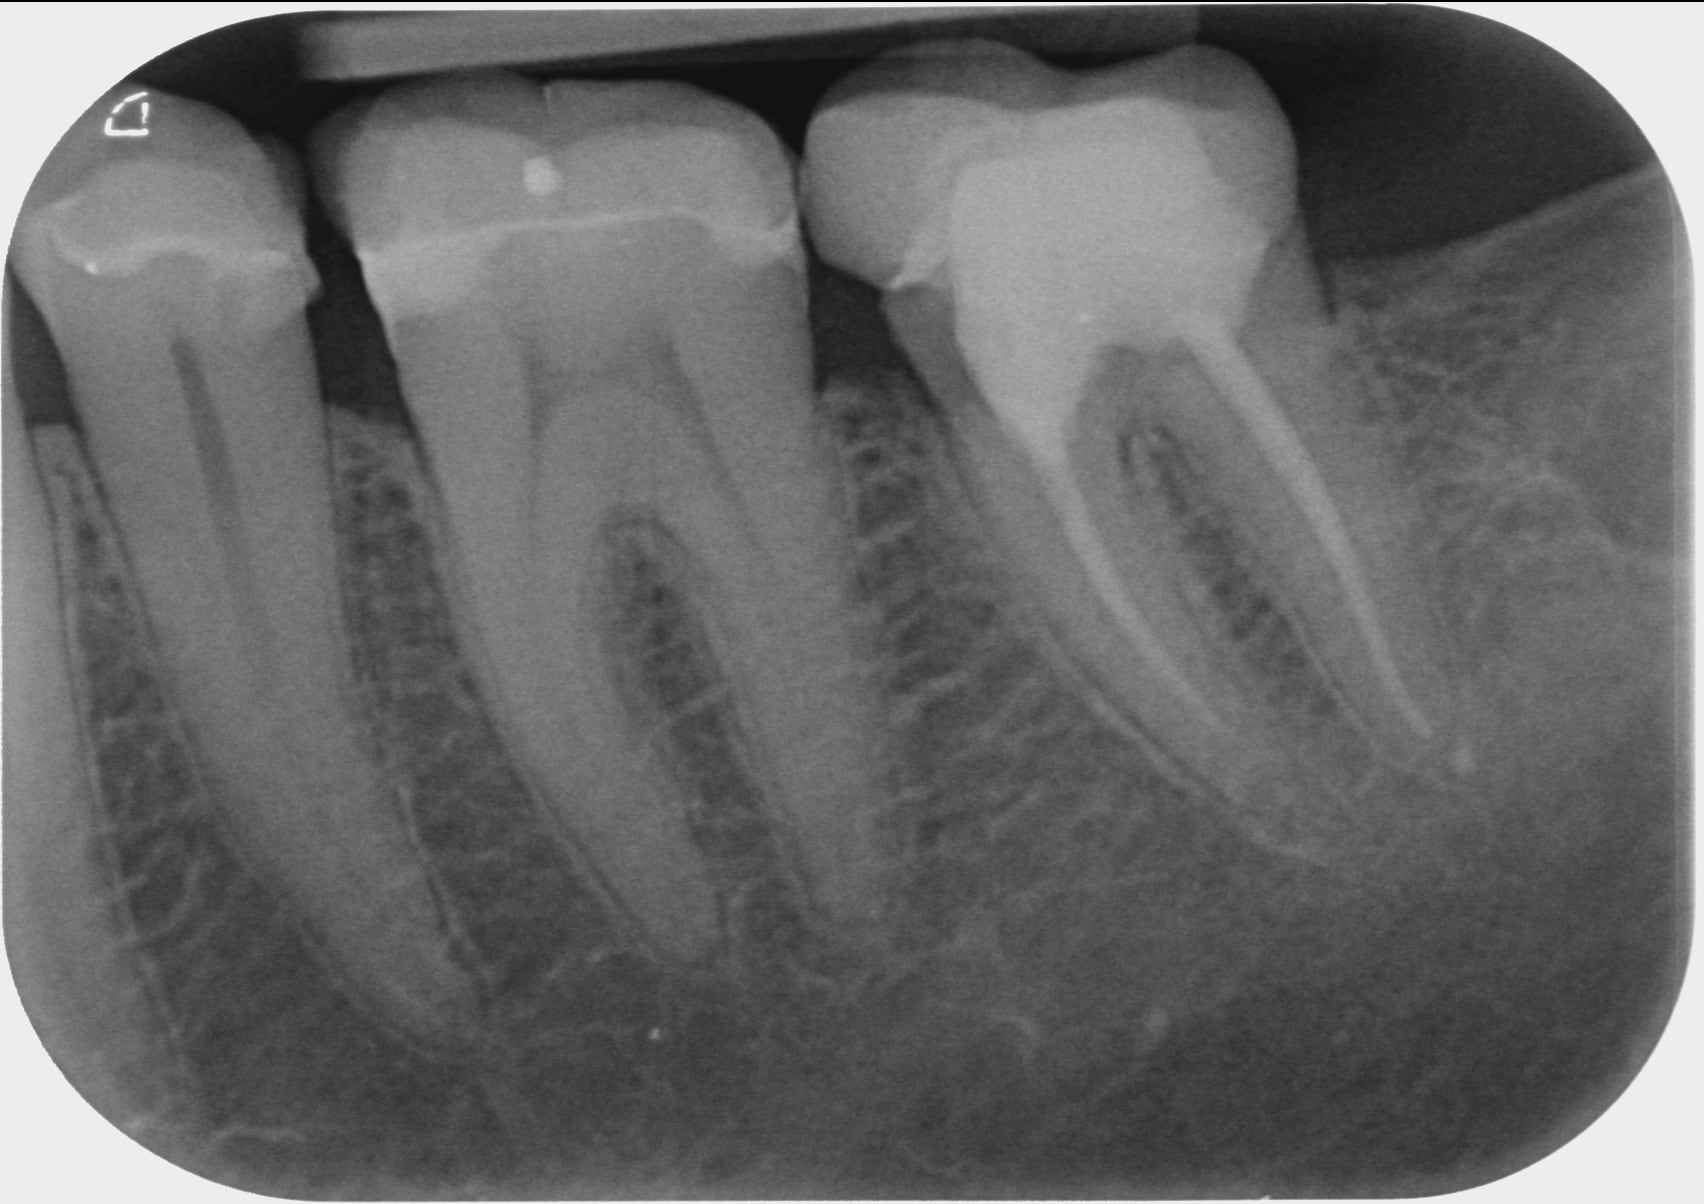

A toutes fins utiles, pour les nouveaux lecteurs, je reposte mes radios.

en ajoutant la 42 également.

Et pourquoi ne pas retraiter la 37 dans un premier temps qui présente une lésion sur la racine mésiale avec un traitement court et une lésion sur la racine distale avec un traitement adéquat?

Bonjour PtnBZ..effectivement l'endo ne va pas jusqu'à l'apex..mais...comme on ne voit pas de tache sombre ..on peut supposer que pas d'infection ?

Le traitement en mésial de 37 n'est pas bon çà se voit tout de suite, peut-être un canal a été oublié, en tout cas un manque d'étanchéité.

Dans un cas comme çà, si cliniquement je vois que la dent est sensible (en écartant la possibilité d'une surocc) et même si le CBCT ne montre rien, je redémonte 37 et refait l'endo, avec le risque effectivement que çà ne change rien mais au moins le traitement sera correct et on peut écarter cette hypothèse à 100%.

C'est marrant que la 37 vous interpelle, alors que la 35 (meme la 45!) est beaucoup plus louche, avec un compo juxta pulpaire (mauvais mariage) , et certainement une mortification lente a bas bruit, le truc bien vicelard au diagnostic differentiel difficile.